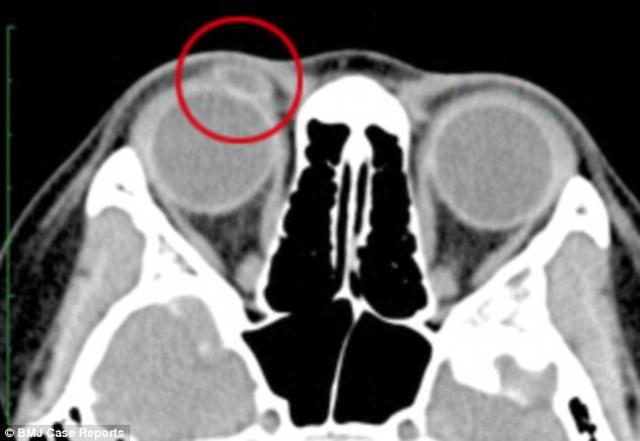

Dikutip dari laman dailymail.co.uk, gadis yang tidak mau disebutkan namanya asal Hong Kong, China ini mengaku bahwa ia sering mengeluarkan noda darah dari matanya saat ia menangis. Tak hanya ada darah, matanya pun juga bengkak dan terasa sakit. Karena kondisi yang aneh inilah ia pun dibawa ke rumah sakit oleh orang tuanya untuk melakukan pemeriksaan. Saat diperiksa dan dilakukan scan terhadap matanya, dokter terkejut dengan apa yang ditemukan di kelopak mata gadis.

Dokter menemukan ada sebuah lensa kontak yang terjebak di kelopak mata. Lensa kontak inilah yang dikatakan sebagai pemicu adanya noda darah saat si gadis menangis. Lensa kontak ini juga yang dikatakan membuat matanya bengkak dan sakit.

Yang lebih mengejutkan lagi, dokter memperkirakan bahwa lensa kontak ini telah terjebak di mata selama lebih dari 1 tahun. Karena telah terjebak dalam waktu yang lama, lensa kontak ini bahkan telah terbungkus kelenjar yang ada di mata dan keberadaannya tidak terlihat secara kasat mata. Si gadis pun juga memberi keterangan bahwa ia pernah kehilangan lensa kontak yang ia pakai kira-kira dua tahun yang lalu. Tapi, ia tidak pernah tahu bahwa lensa kontak yang hilang justru terjebak di kelopak matanya sendiri.